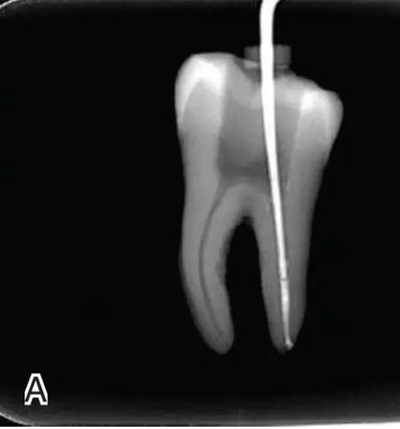

要求工作尖能自由到達(dá)距根尖4~5 mm(有學(xué)者提出3~4 mm)的位置并能輕微接觸根管壁,用橡皮片做好標(biāo)記(圖1)。

圖1 選擇攜熱器工作尖,A.試攜熱器尖 B.工作尖在根內(nèi)的位置